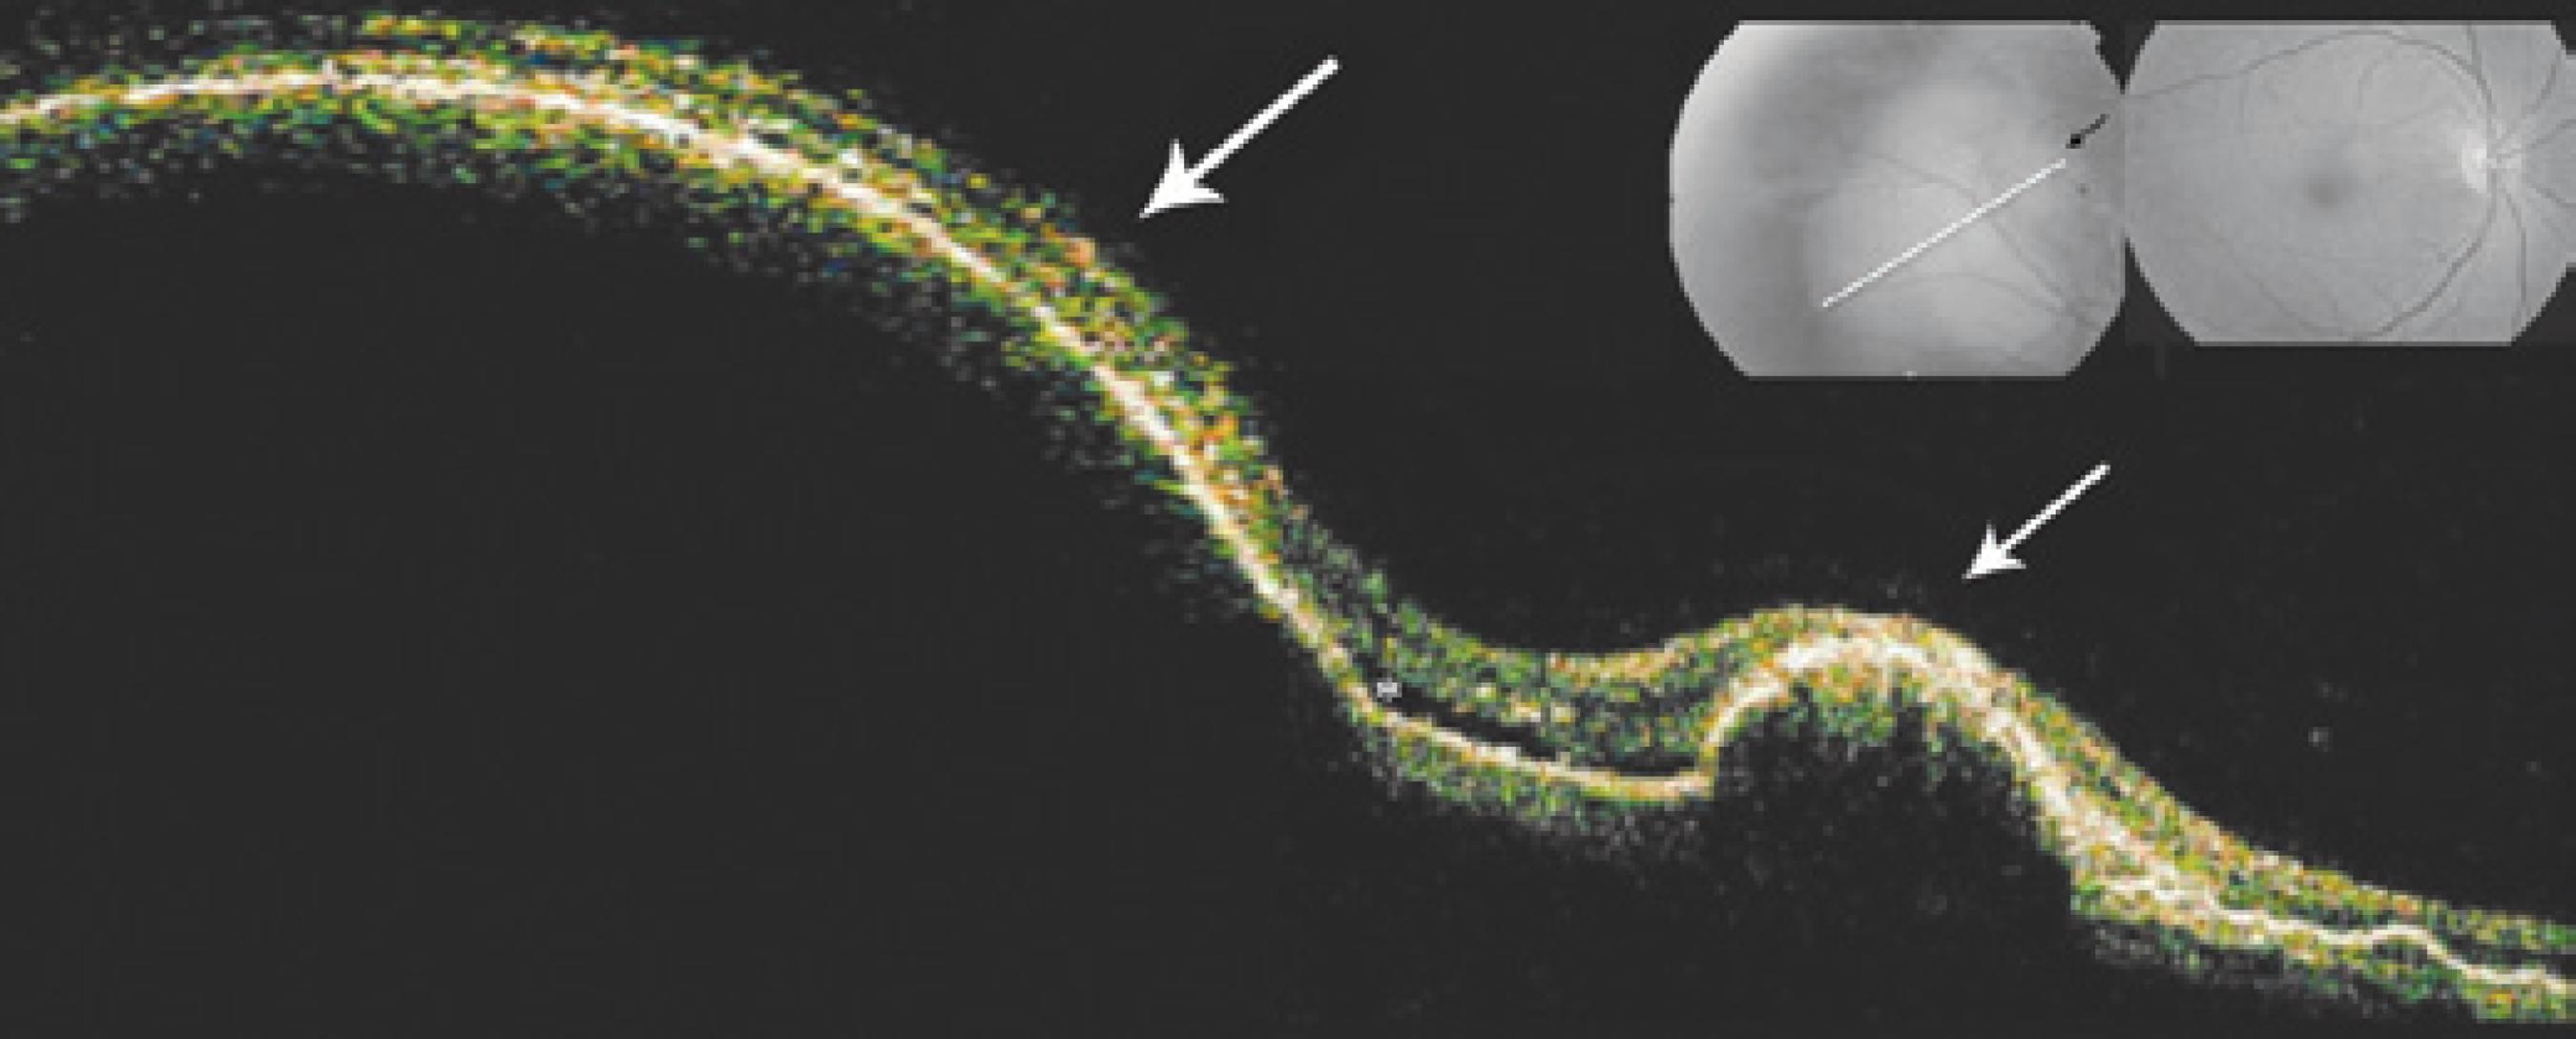

The OCT examination of the major lesion in OD revealed a large PED with adjacent smaller lesions resembling a vascular tumor, and these observations were correlated with retinal serous detachment (Figure 2). Fluorescein angiography of OD showed a patchy area of subretinal staining of undetermined origin, with minimal leakage and a blockage area corresponding to the elevated lesion (Figure 1B). ICG revealed the presence of an inner choroidal vascular abnormality that ended in multiple small, hyperfluorescent polyps with leakage characteristic of IPCV, as well as a permanent blockage area observed during all phases of the angiogram, which corresponded to the major PED (Figure 1C). No macular changes were observed. One year later, there was decreased dimension and discoloration of the lesions, which now resembled a choroidal osteoma (Figure 3). After the initial visit no treatment was administered, because the macula was not threatened.

Figure 2. OCT showing the larger lesion, represented by the long white arrow, and the smaller lesion, represented by the short white arrow, corresponding to hemorrhagic pigment epithelium detachments (PED). Note the presence of serous retinal detachment, as shown by the asterisk, and multiples areas of PED on the right.